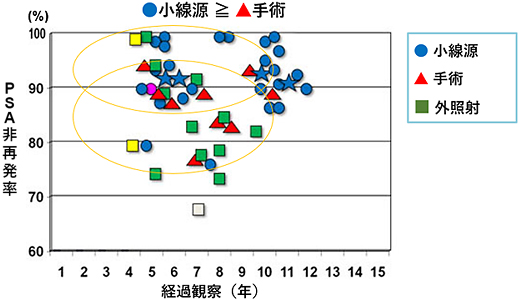

前立腺がんのリスク別の治療効果

低リスクがん

低リスクがんの場合、10年で考えれば●小線源と▲手術単独では※PSA非再発率は大きな差はありません。

※臨床的再発の前にPSAのみの持続的な上昇が認められ、カットオフ値以上になること